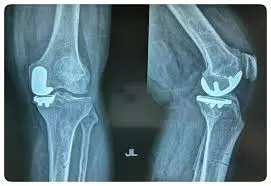

At Numed Hospital, we specialize in Partial/Unicondylar Knee Replacement, an advanced surgical procedure designed for patients suffering from knee arthritis that is limited to a single compartment of the knee. Unlike total knee replacement, this minimally invasive technique preserves healthy bone and tissue, allowing for a more natural knee function and quicker recovery.

Patients with localized osteoarthritis, intact ligaments, and stable knee alignment are ideal candidates for this procedure. Our orthopedic specialists conduct thorough assessments, including imaging and physical evaluations, to determine the best course of treatment.

A partial knee replacement is better for patients with localized arthritis, offering faster recovery, less pain, and preserved knee function compared to total knee replacement.

Total knee replacement replaces the entire knee joint, while unicondylar knee replacement preserves healthy structures by replacing only the damaged compartment, leading to faster recovery and natural movement.